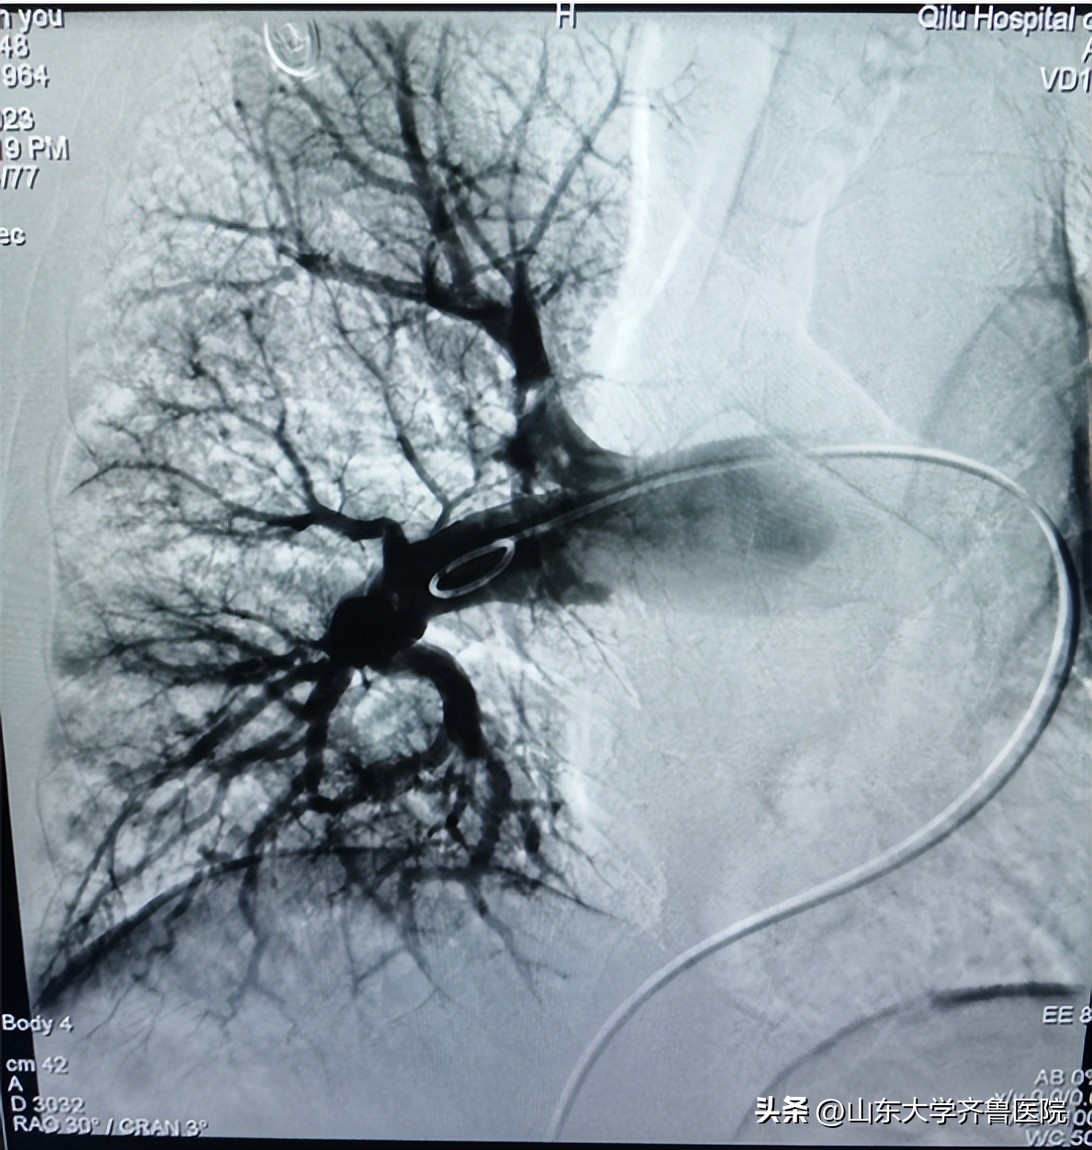

手术将血栓抽吸导管沿导丝推送至右肺动脉干后进行抽吸,抽出大量条状及块状红色血栓;再将肺动脉取栓系统在残余栓块中释放网盘支架,吸附残余栓子后回收至抽吸导管;造影见右肺动脉血栓清除率约70%,血流通畅PFG3级,术后测肺动脉压力明显下降。经血管造影确认血栓清除达到目标后结束手术。国产SIRIUS TWIFLOW®肺动脉取栓系统与血栓抽吸导管的联合治疗急性肺栓塞具有显著的临床效果,同时操作简单、手术时间短、安全性高等特点。